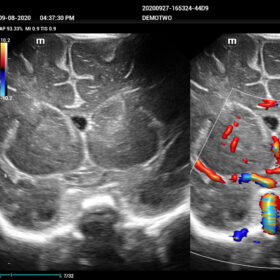

Comprehensive Imaging Solutions Powered by ZST+

The ZST+ platform is a remarkable advancement, marking a significant evolution in ultrasound technology. It revolutionizes the processing of ultrasound metrics, moving away from the traditional beam-forming approach to channel data-based processing. This breakthrough eliminates the longstanding trade-off challenges between spatial resolution, temporal resolution, and tissue uniformity. The result is outstanding image quality, providing limitless imaging solutions with continuous enhancements.

- Smart HRI– Automatic regognition of liver and renal cortex and brightness ratio calculation

- NTE – ROI stiffness display with “Shell” quantitive assesment

- HD-Scope – improving diagnostic confidence of minor lessions

- Dehaze-improving image contrast resolution with deep presentation

- HR-Flow Improving the hemodynamic presentation